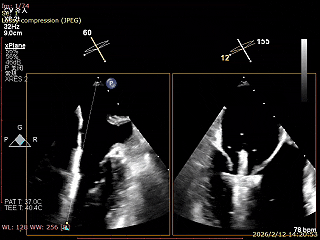

二尖瓣术前评估

复查TTE及TEE检查进一步评估二尖瓣情况。明确为AFMR,二尖瓣功能性反流,2区瓣叶运动,重度FMR(3+),肺静脉逆向血流;2区后叶长度13 mm,2区前叶长度20mm,AP径37mm,瓣口面积4.08cm²,房间隔高度4.5cm,瓣叶无钙化,二尖瓣瓣膜条件适合行TEER手术。

术前Bicom

二尖瓣2区功能性反流